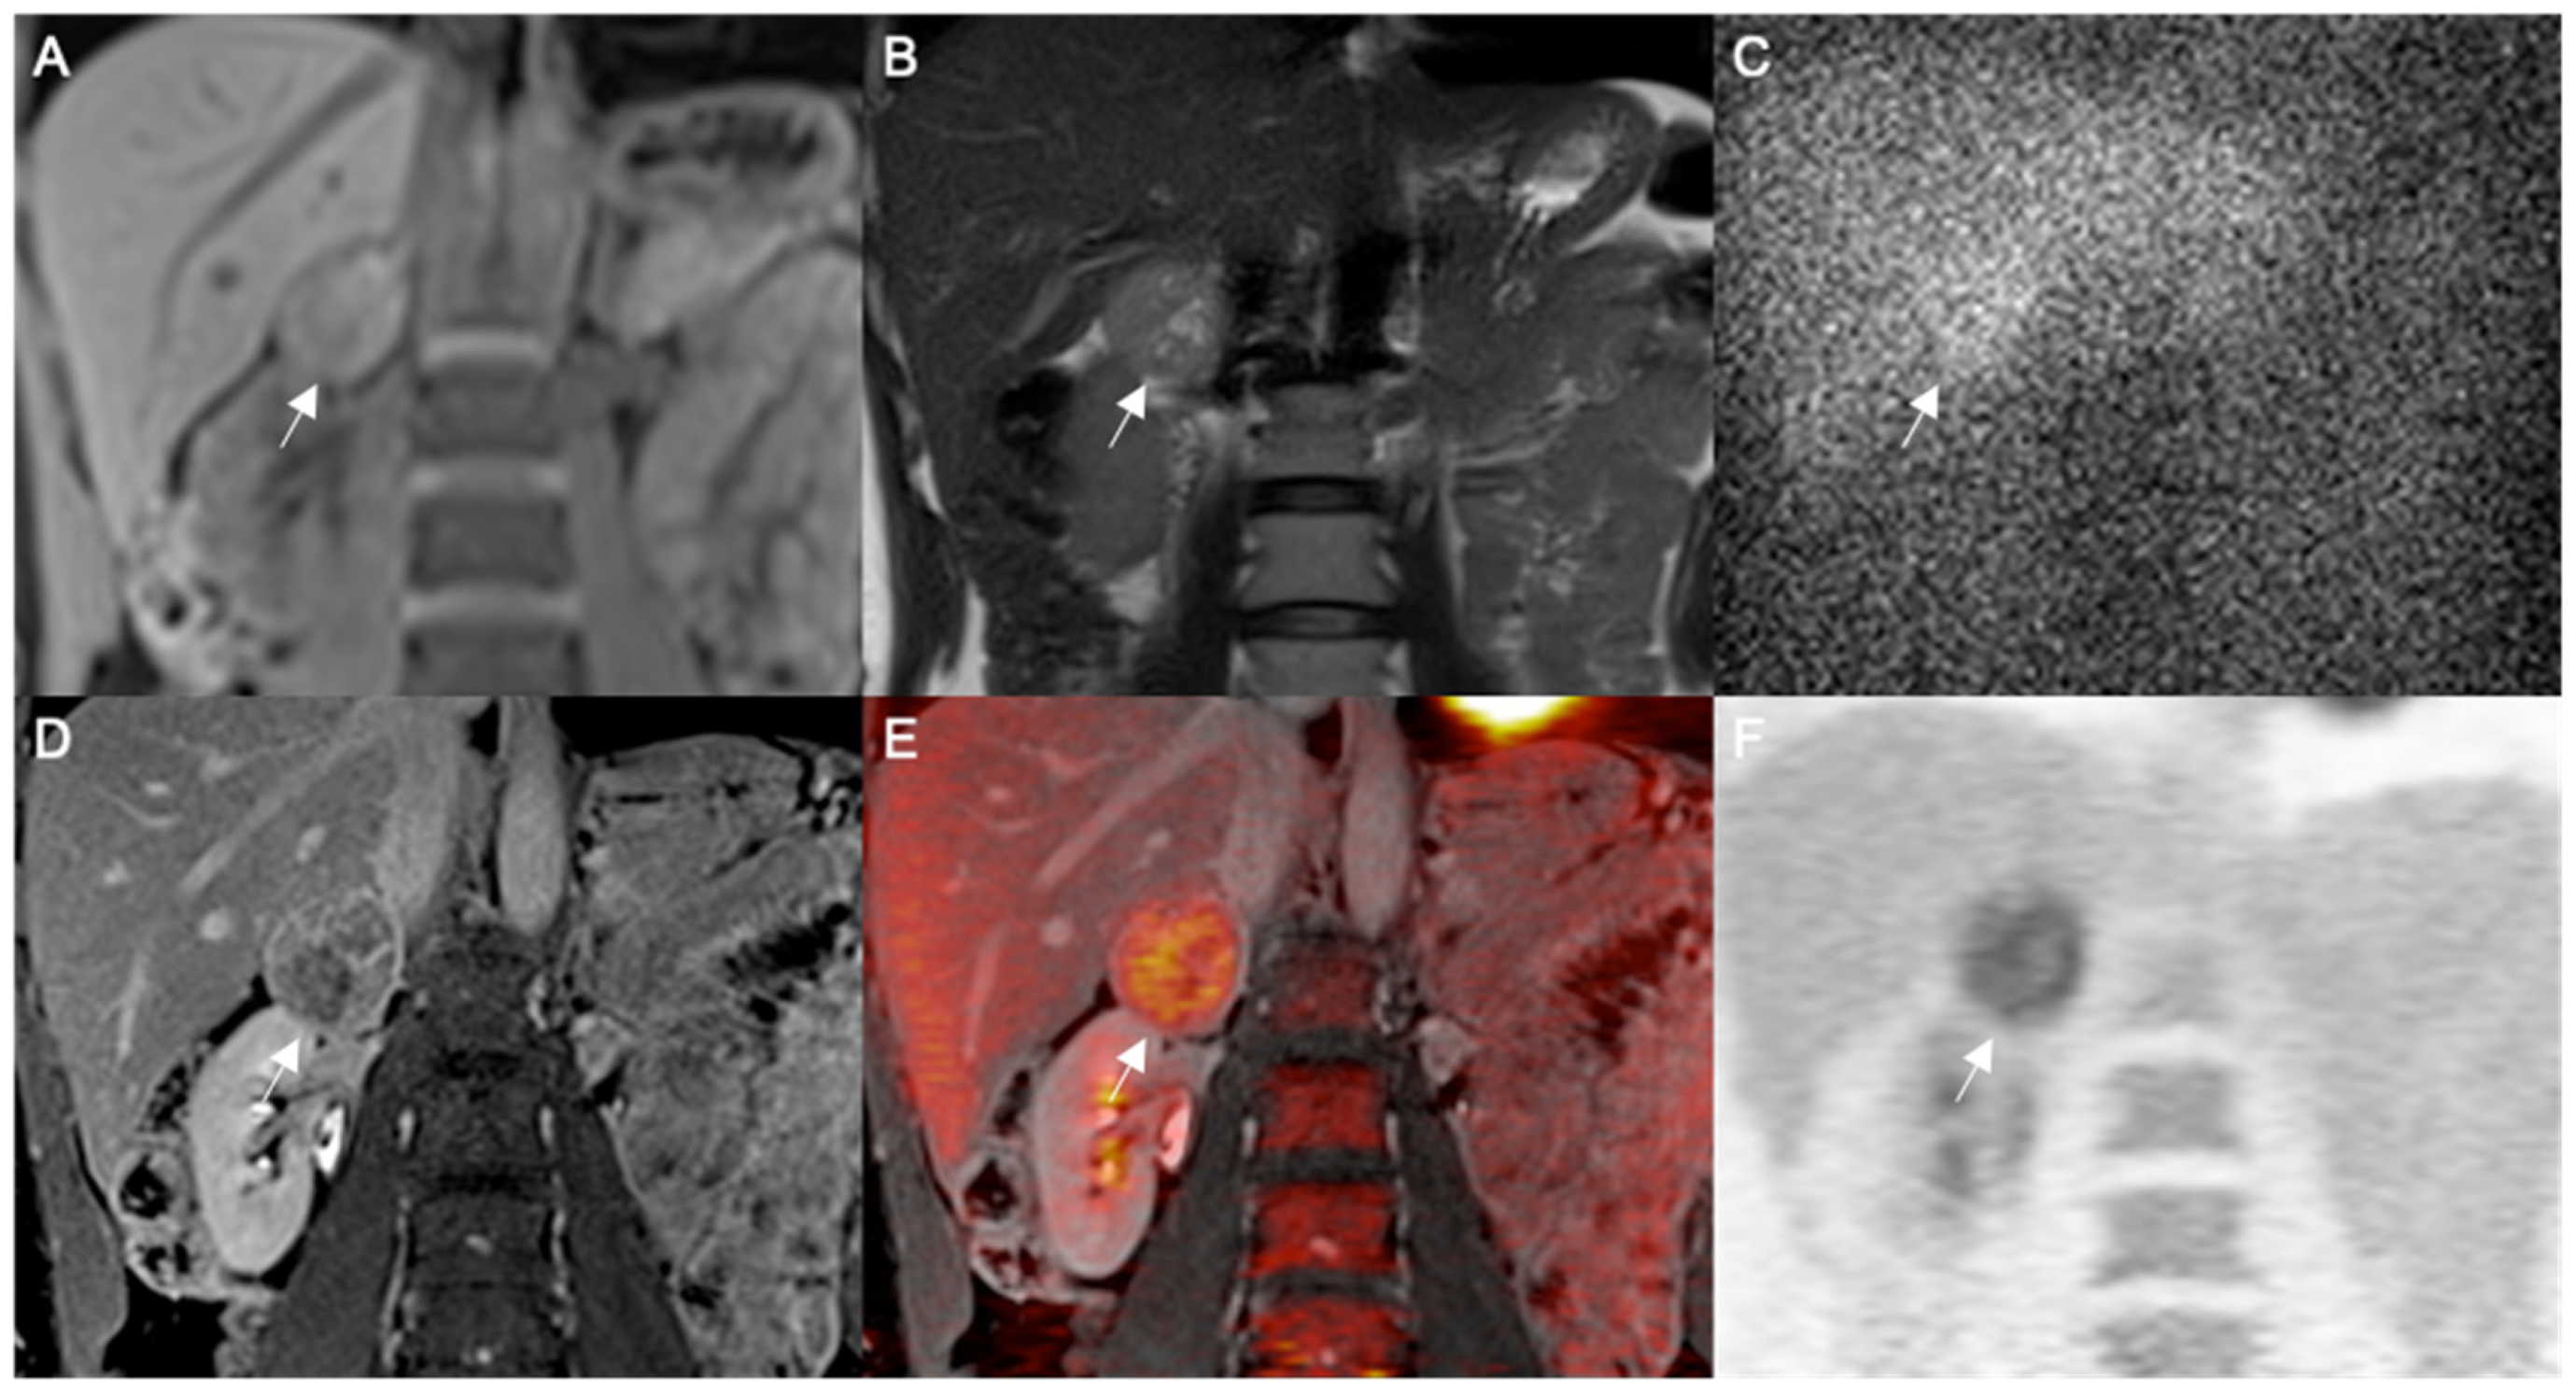

Figure 1. Large right adrenal totally cystic pheochromocytoma. MRI coronal images represented by T1-WI FS enhanced (A) and T2-WI (B) show a cystic large adrenal mass with capsular contrast enhancement measuring 7 cm (arrows). Planar adrenal scintigraphy with 131I MIBG in anterior view at 48 h after tracer injection (C) shows inhomogeneous tracer uptake in the adrenal lesion, more evident in the capsular rim thickened on the left side (arrow). 18FDG PET-CT coronal image shows a hypodense large adrenal mass with regular margins (arrow) on unenhanced CT scan (D); hybrid fused PET-CT image (E) shows faint increased irregular FDG uptake only in the peripheral rim of the lesion as also confirmed by the extracted FDG image (F) (double arrows).

In particular, MIBG scans were available in five tumors of which four (80%) showed abnormal heterogeneous residual tracer uptake (one totally cystic, one predominantly cystic, one partially cystic and one hemorrhagic), while the last one (predominantly cystic) was falsely negative. 18F-FDG PET/CT was performed in six lesions showing tracer uptake only by the residual solid component or peripheral rim of tumor structure, of which one was totally cystic, two predominantly cystic, one partially cystic and two hemorrhagic.

18F-FDG PET/MR was performed in two lesions showing tracer uptake only by the residual solid component or peripheral rim of tumor structure, of which one was totally and one was partially cystic. The results of hybrid 18F-FDG imaging showed heterogeneous tracer uptake in the 100% of tumor lesions (n = 8). In these lesions the measurement of SUV max ranged from 1.6 to 10.5. Imaging examples of totally or partially cystic pheos are shown in Figure 1 and Figure 2, respectively.